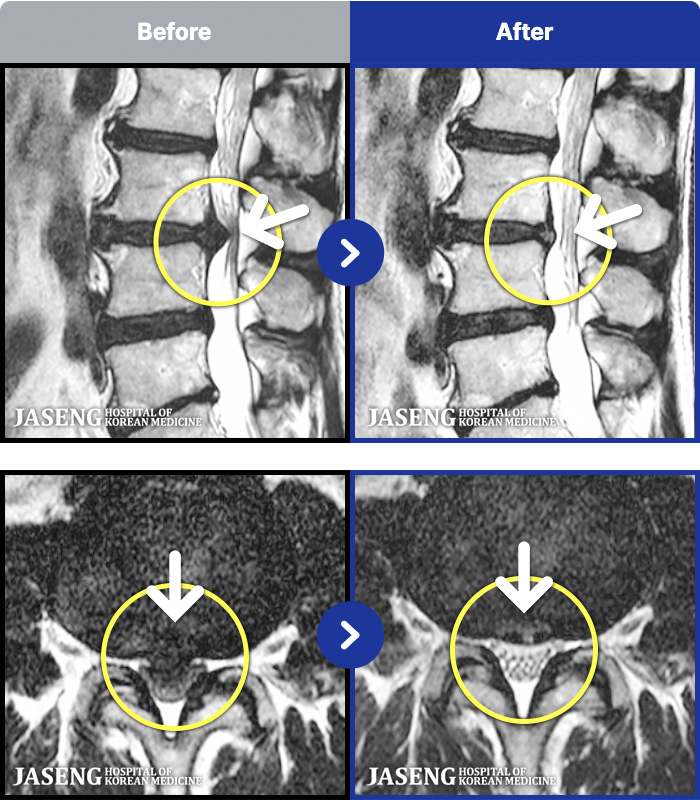

MRI ġ

1,301 MRI ũ ʸ Ȯϼ.